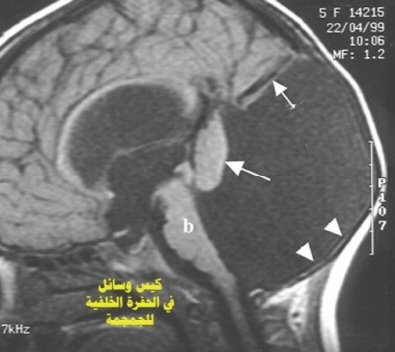

بمجرد أن يقترب من كيس مليء بالسائل الأزرق ، يتم دفع #الروبوت بسرعة الصاروخ ليخترق الكيس بنهايته المدببة، مما يسمح للسائل بالتدفق.

كما تتكون أكياس بحجم كرة الجولف عند المصابين بالأمراض الخلقية، و تورم مما يسبب ضغط متزايد على الدماغ، ويؤدي إلى ظهور مشاكل عصبية خطيرة.